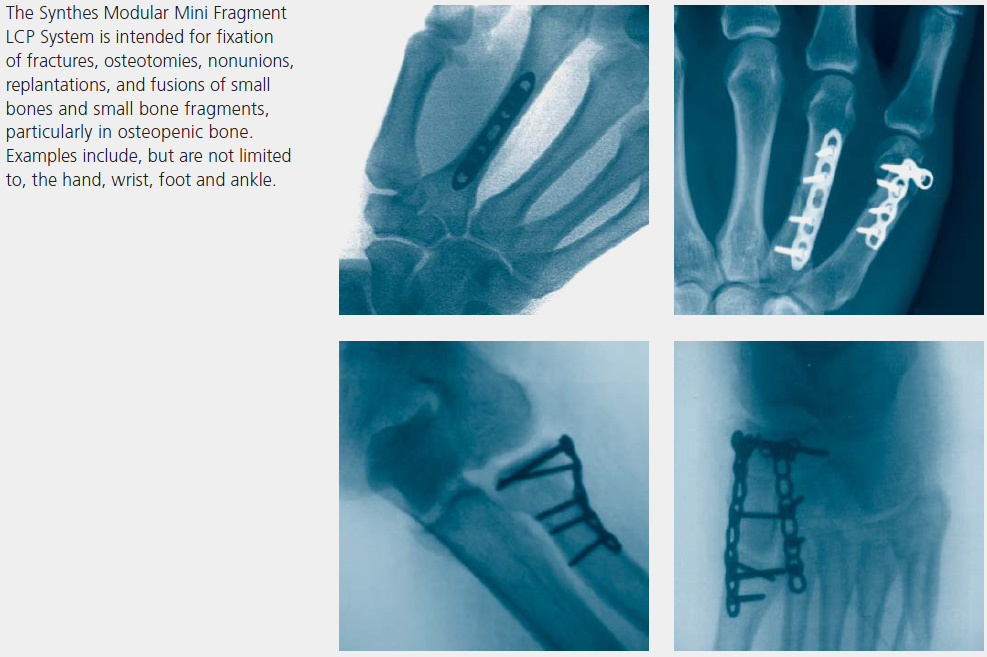

Indications